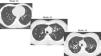

The Bhalla score evaluates the severity of bronchiectasis, peribronchial thickening, extension of bronchiectasis (number of pulmonary segments), extension of mucus plugging, sacculations and abscesses, involvement of bronchial generations, number of bullae, emphysema, and collapse/consolidation. Instead of assessing emphysema and its extension, we evaluated the extent of air trapping in the expiratory sections (Table 1). The points in each category vary from 0 to 3. The sum of the score obtained for each item was subtracted from 25 in order to obtain the overall Bhalla score. Different examples of Bhalla scores are shown in Fig. 1.7

Axial CT images of pulmonary window in different patients with CF and different Bhalla scores. Bhalla 23 is an example of a mild disease with mild bronchiectasis while Bhalla 16 presents a moderate disease with mucous plugging and bigger bronchiectasis. Finally, Bhalla 10 shows a severe disease with sacculations, greater thickness wall and higher luminal diameter of bronchiectasis, also with mucous plugging and air trapping.